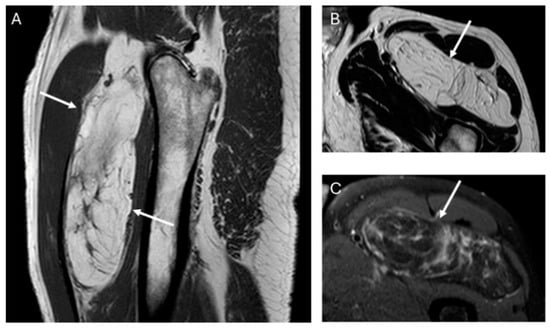

In our series, the lipomas showed both homogeneous and heterogenous fat signal intensity, while all ALTs were heterogenous tumors. Based on this criterion—the signal intensity of the tumor on MRI—some lipomas may be misinterpreted as ALT, but the opposite is not true; no ALTs would be misdiagnosed as a lipoma. With homogeneous hyperintensity on SE T1 and TSE T2 sequences, and complete suppression of the fat signal using fat suppression techniques, the diagnosis of lipoma can be made with high confidence. In contrast, heterogeneous tumors may be either a lipoma or an ALT (Figure 4) Therefore, homogeneous signal rules out ALT, while heterogeneous signal does not rule out lipoma (Figure 1).

Figure 4.

Top: Heterogeneous lipomatous mass in the posterior compartment of the thigh, measuring 22 cm, with multiple thick septa visible on T1 and T2 (A,B) and showing incomplete suppression on DP SPAIR (C). These MR findings are consistent with a radiological diagnosis of ALT. Final diagnosis: ALT (MDM2 positive). Bottom: Lipomatous tumor in the left lateral vastus, measuring 14 cm, with thin septa visible on T1 and T2 (A,B) and incomplete suppression on DP-SPAIR (C), leading to a radiological diagnosis of uncertain lipomatous tumor (lipoma versus ALT). Final diagnosis: lipoma (MDM2 negative).